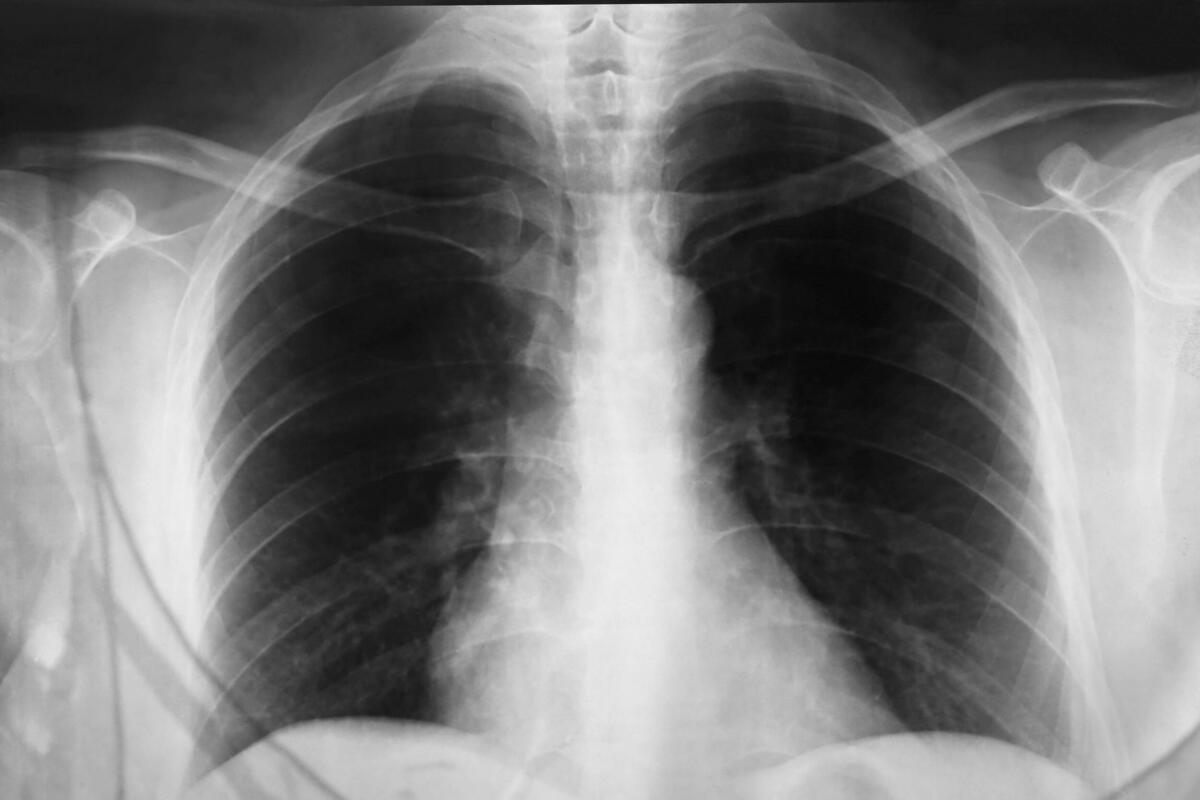

Pluća, Foto: Mohammed Anwarul Kabir Choudhury / Alamy / Alamy / Profimedia